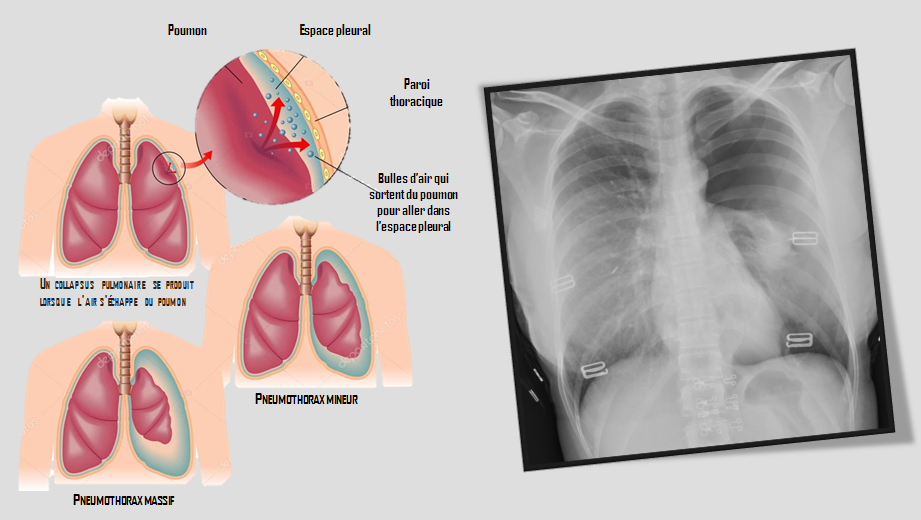

Les pneumothorax sont des pathologies fréquemment rencontrées dans les services d’urgence. On parle de pneumothorax lorsqu’il y’a une accumulation d’air entre les deux feuillets de la plèvre.

Il existe trois formes de pneumothorax :

• Le pneumothorax spontané primitif (P.S.P.) : Il survient généralement chez des sujets jeunes, souvent sveltes et longilignes (corps de trailers, avec des poumons sains et décrivant pour certain un phénotype marfanoïde (habitus marfanoïde :  patient grand, hyperlaxe, faisant écho à la maladie de Marfan). Le phénomène se produit lorsqu’une bulle d’air se forme à la suite d’une (petite) fuite d’air au niveau sous pleural à la suite d’un barotraumatisme (avion, plongée, ou éternuement nez bouché, ce qui empêche la perte de pression). Cette fuite d’air peut guérir spontanément lorsqu’une accumulation de fibrine se forme à l’orifice, agissant schématiquement comme une rustine.

• Les pneumothorax spontanés secondaires (P.S.S.) : Contrairement au pneumothorax primitif qui concerne des poumons sains, le pneumothorax spontané secondaire survient chez des patients qui ont déjà une pathologie qui fragilise les poumons. En général, il s’agit de patient plus âgés, atteint de pathologie respiratoire chronique (B.P.C.O., emphysème…), qui majore le risque de complications et les exposent à une mortalité plus forte (d’environ 15 %). Ces pneumothorax peuvent être révélateurs d’une autre pathologie pulmonaire à contexte généralement infectieux : infection pulmonaire, tuberculose… ou même d’un cancer pulmonaire. Le tableau clinique met en exergue l’altération fonctionnelle de la fonction respiratoire. Ce type de pneumothorax peut rapidement montrer un tableau de dyspnée asphyxiante, qui peut se révéler être une vraie situation d’urgence.

• Les pneumothorax traumatiques (P.T.) : Ces pneumothorax sont faciles à diagnostiquer compte tenu du contexte traumatique associé. Le traumatisme peut être direct ou iatrogène (à la suite d’un acte médical). Ils sont à envisager à la suite d’un traumatisme récent avec une dyspnée majorée à l’inspiration (sans désaturation obligatoire).

Le pneumothorax peut se présenter de plusieurs manières, à la fois par des signes extérieurs visibles et des signes présents lors de l’auscultation. Si le pneumothorax est discret, il peut même se présenter sous une forme asymptomatique. Après la recherche d’absence de signes de gravité, les autres signes cliniques peuvent être recherchés, confirmés par l’imagerie.